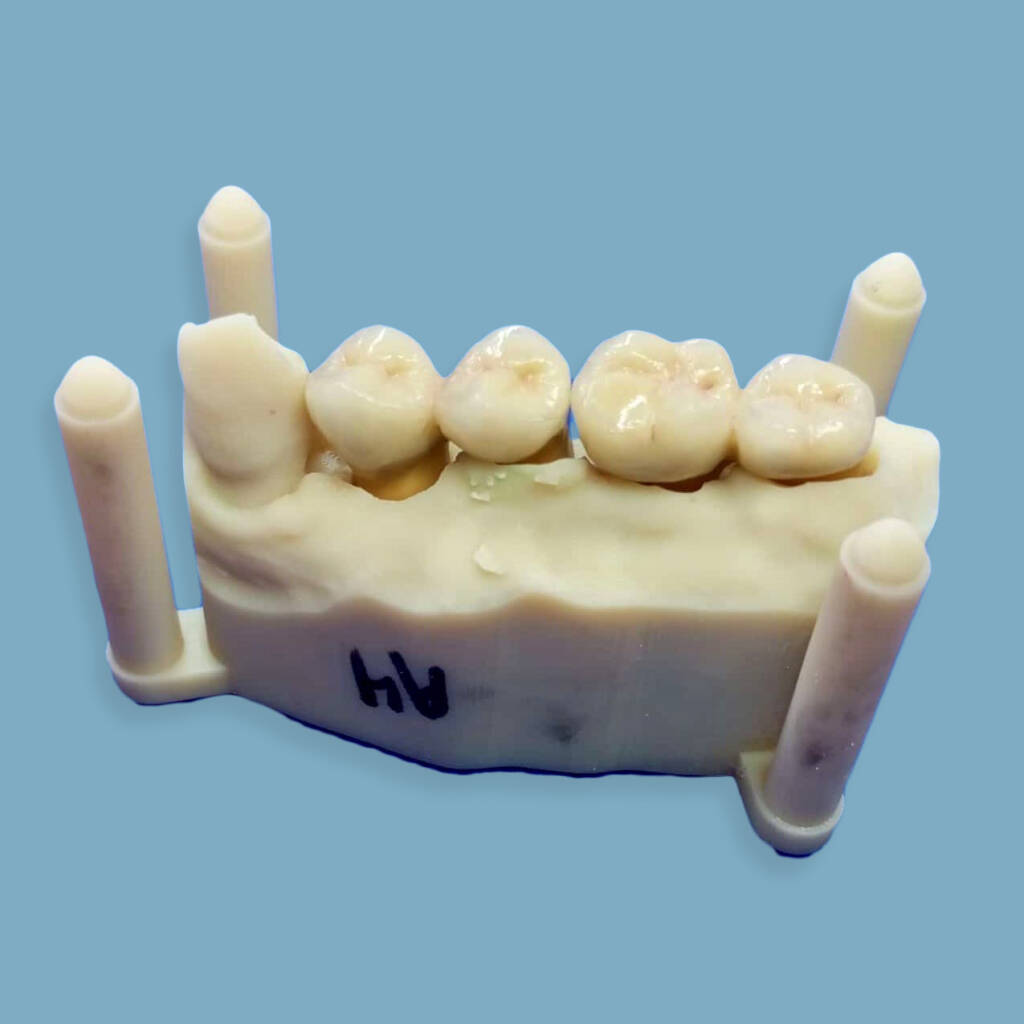

Expertise et polyvalence dans les systèmes implantaires et types de connectiques : hexagonales, internes ou externes. Notre savoir-faire englobe une large gamme de réalisations : couronnes, bridges, piliers implantaires, mises en charge immédiates et finitions sur barres implantaires. Nous travaillons divers matériaux comme le chrome-cobalt, le titane, la zircone pour garantir des solutions durables et sur mesure.

Implantologie conjointe